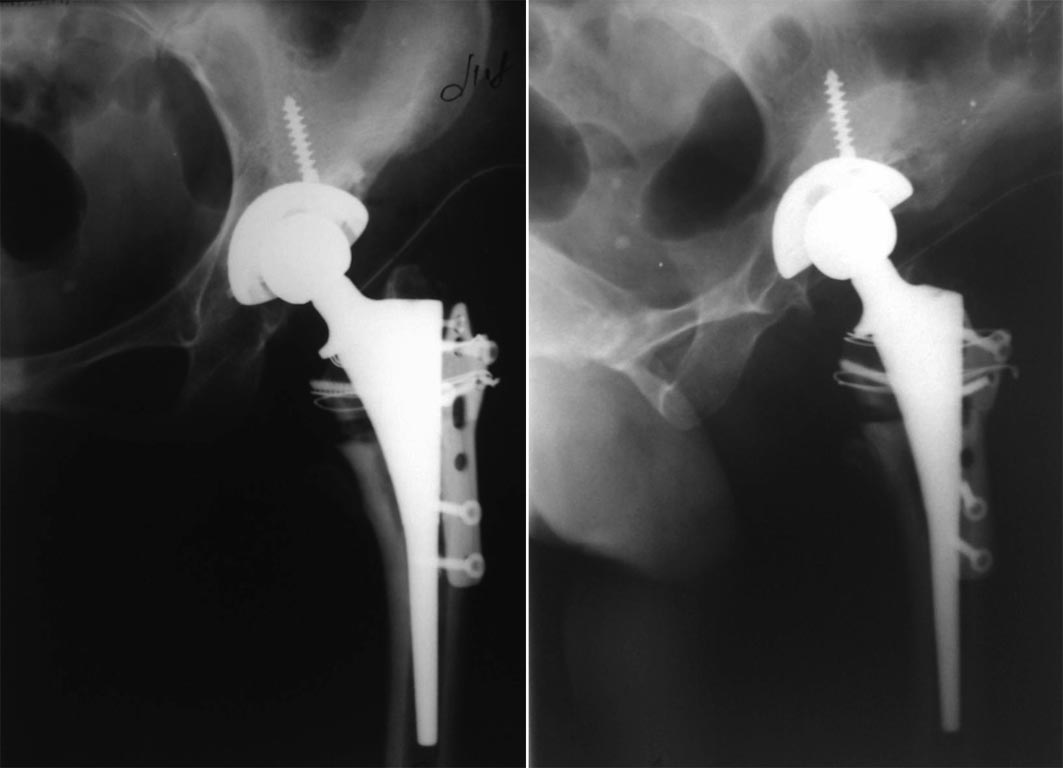

Мы в подобном случае  поступили следующим образом (укорочение тоже было

значительным, но обошлось без осложнений):